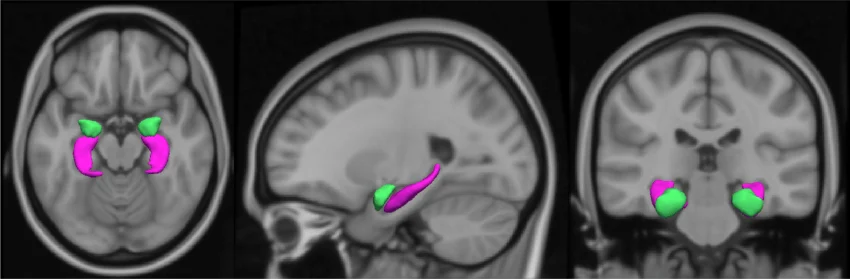

Exhibit 1: T1-weighted MRI scan (axial, sagittal, and coronal view) showing the amygdala in green. Via ResearchGate

The amygdala is a small, almond-shaped structure deep in the brain responsible for processing threat and emotional stress. In people with depression or anxiety, brain imaging shows a measurably higher amygdala-to-cortex activity ratio, meaning the stress alarm fires louder and longer than in people without these conditions.

A 2017 Lancet study, among the first to directly link regional brain activity to cardiovascular outcomes, found that for every one standard deviation increase in amygdala activity, cardiovascular disease risk increased by nearly 60%. The amygdala also signals the bone marrow to produce extra white blood cells, which travel to arterial walls and drive the plaque buildup underlying most heart attacks and strokes.